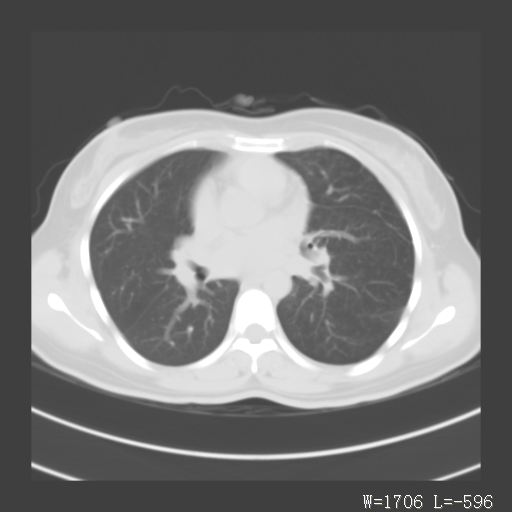

1)考虑左肺上叶肺脓肿,节段性肺不张。2)永存左上腔静脉。

1)考虑左肺上叶节段性肺不张。原因?2)永存左上腔静脉。

考虑左肺上叶胸腺瘤可能性大。肺不张/永存左上腔静脉

胸骨后偏左侧囊实性病灶,考虑胸腺瘤可能性大.

1、胸骨后偏左侧囊实性病灶,考虑胸腺瘤可能性大。2、永存左上腔静脉。